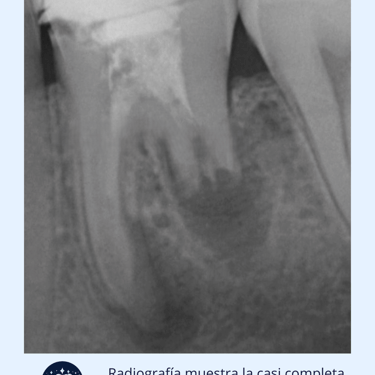

Radiografías: Se toman radiografías para visualizar el grado de reabsorción en la raíz del diente. En algunos casos, puede ser necesaria una tomografía computarizada (CBCT) para obtener imágenes más detalladas.

Resultados esperados: Si la reabsorción es leve, el diente puede ser tratado con endodoncia. Si es extensa, puede ser necesario extraer el diente.